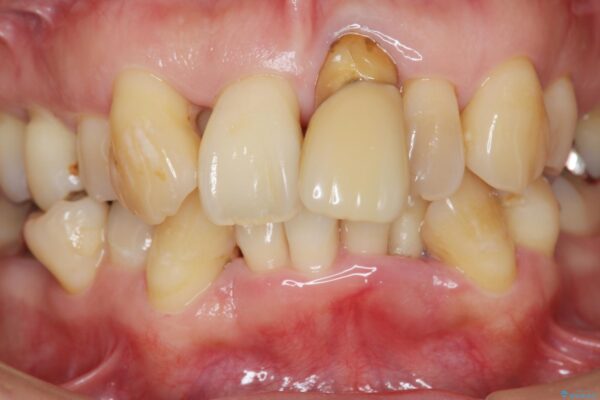

治療前

歯の総合的なマネージメントを行う包括的歯科治療の実践[ 歯周病・矯正・セラミック補綴 ] 治療前画像 歯の総合的なマネージメントを行う包括的歯科治療の実践[ 歯周病・矯正・セラミック補綴 ] 治療前画像 歯の総合的なマネージメントを行う包括的歯科治療の実践[ 歯周病・矯正・セラミック補綴 ] 治療前画像 歯の総合的なマネージメントを行う包括的歯科治療の実践[ 歯周病・矯正・セラミック補綴 ] 治療前画像 歯の総合的なマネージメントを行う包括的歯科治療の実践[ 歯周病・矯正・セラミック補綴 ] 治療前画像 歯の総合的なマネージメントを行う包括的歯科治療の実践[ 歯周病・矯正・セラミック補綴 ] 治療前画像 歯の総合的なマネージメントを行う包括的歯科治療の実践[ 歯周病・矯正・セラミック補綴 ] 治療前画像